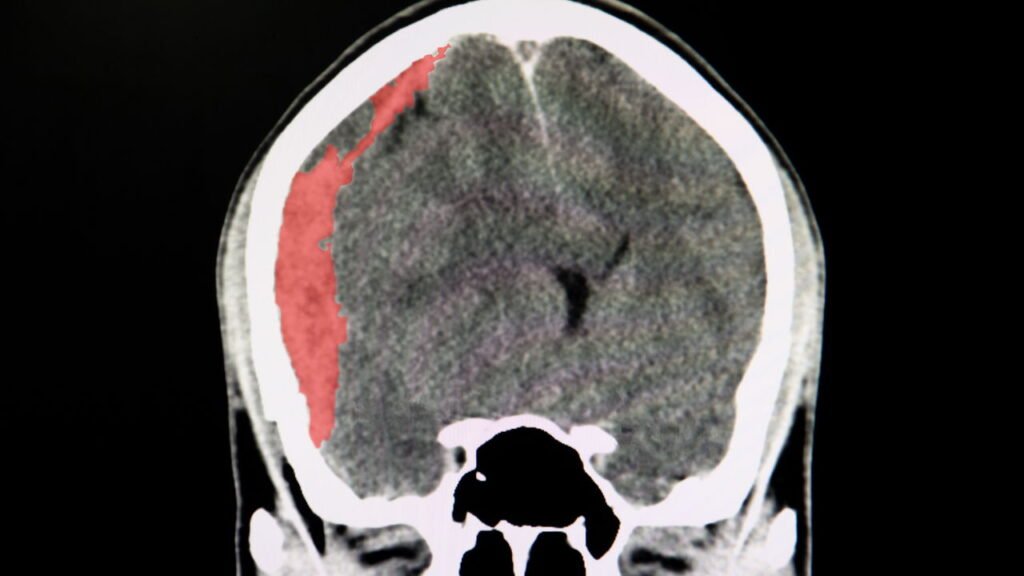

Em casos extremos, o cérebro pode inchar, causando edema cerebral, uma emergência médica com risco de morte.

Beber pouca água é perigoso, mas quão perigoso é beber água demais?

Imagem de edema cerebral – Créditos: depositphotos.com / navuths@gmail.com

Edema cerebralInchaço no cérebro devido à diluição de eletrólitos.Risco de coma ou morte.